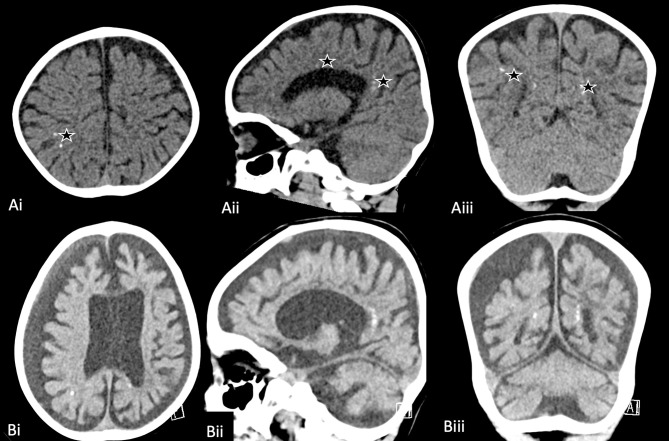

Negative regulator of reactive oxygen species (NRROS)-related microgliopathy (MIM# 618875) is a rare autosomal recessive neurodegenerative disorder. This case report describes a Saudi Arabian child with a novel homozygous NRROS variant, NM_198565.2: c.257T>C (p.Leu86Pro) presenting with drug-resistant epilepsy, rapid developmental regression, microcephaly, dystonia, and intracranial calcifications. Neuroimaging revealed bilateral intracranial calcifications, generalized brain volume loss, and connatal cysts; EEG showed a slow, suppressed background with multifocal epileptiform discharges. The variant is predicted to be deleterious by multiple in silico tools, suggesting a pathogenic effect on microglial function. This case underscores the importance of considering NRROS-related microgliopathy in children with early-onset neurodegeneration, drug-resistant epilepsy, and intracranial calcifications, enabling targeted genetic testing, diagnosis, and counseling.